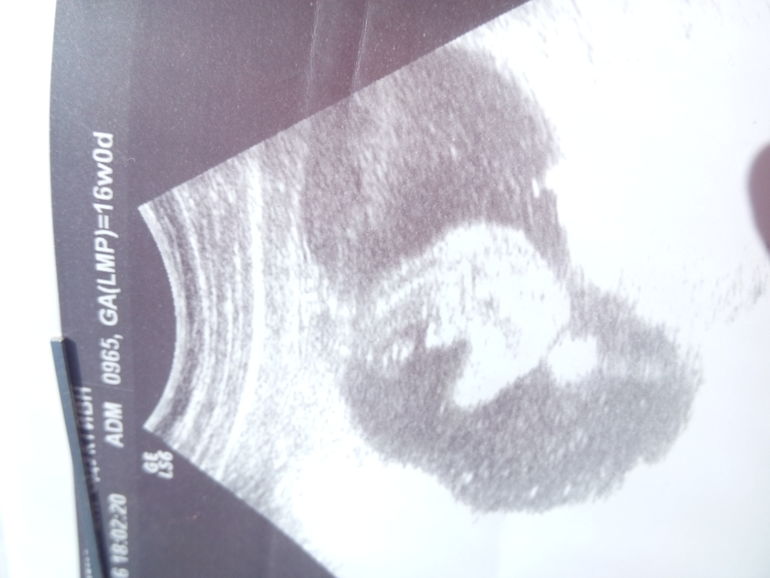

Вопросы про УЗИ, обследования и анализы: что, где, как, когда?Была на УЗИ в 16 недель. Мне врач сказал что малыш похож на мальчика. А вы как думаете?

Если узист на все сто уверено сказал- значит мальчишка! А фото похоже на парня, но это может быть и что то ещё, пуповина например

Если (а в 16 недель, уже половой бугорок формируется в определённое) сформировалось все, то похоже сынок)

Она сказала что пуповина рядом, но на 100 процентов типо надо в 20 недель смотреть. Всем спасибо за комментарии,сама я знаю что сына жду, так как мы его планировали очень тщательно. Вообще на следующем УЗИ посмотрим.)))